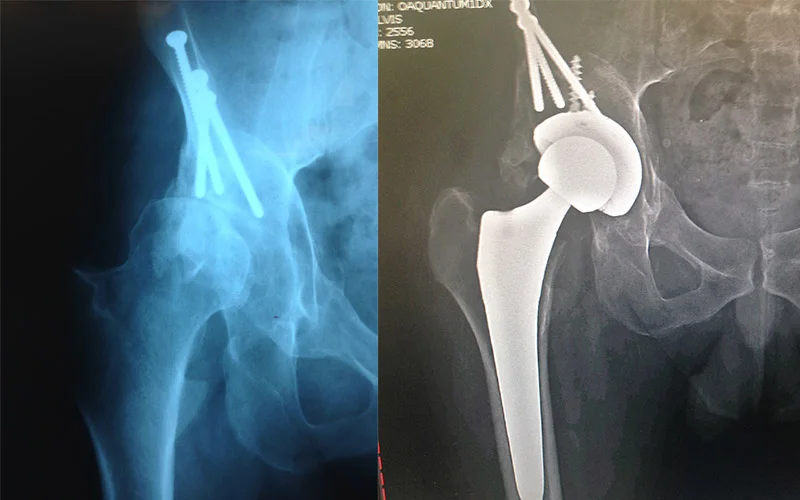

Before: Previous osteotomy surgery with screw fixation for dysplasia - now very arthritic and bone on bone

After: Total Hip Replacement

OMNI